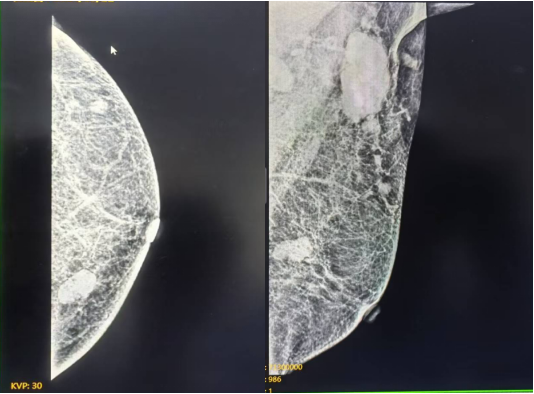

穿刺病理结果(2024年05月22日 我院):

图 穿刺病理结果(2024年05月22日 我院)

(左乳11点结节)浸润性癌。

(左侧腋窝淋巴结)可见癌转移。

免疫组化结果:ER (90%,+++), PR (80%,+++), Ki67(40%+), CK5/6(-), P63(-), E - cad (+), P120(膜+), AR (+), EGFR (-), Her-2(0), GATA3(+), CK14(-), GCDFP -15(+)。

穿刺病理结果(2024年05月24日 我院):

图 穿刺病理结果(2024年05月24日 我院)

(右侧胸壁结节)穿刺组织内见条索样、腺样排列的肿瘤细胞,细胞具有异型性,结合病史及免疫组化表型,符合乳腺癌转移。

免疫组化结果:Ckpan(+),GATA3(+),GCDFP-15(+),ER(90%,+++),PR(80%,+++),Her-2(0),Ki67(30%+),S100(-),Mammaglobin(-),Myogenin(-),MyoD1(-),Vimentin(-)。